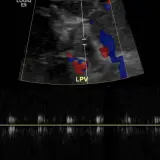

Ultrasound

75 cases Covering OB/GYN, GI/GU, and more